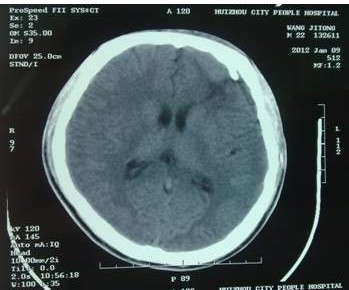

2011年12月,一位患者几经辗转慕名来到我院,求助于余永强主任。患者为年轻男性,是一名汽修厂工人,由于工作时轮胎爆炸导致头部受伤,外院CT提示额骨左侧粉碎性骨折并左额叶脑内血肿,血肿量约40ml,已经达到了开颅手术指征(图1)。当地医院拟予开颅手术。但是家属考虑到开颅手术的风险,同时,由于额骨粉碎性骨折,如果接受传统开颅血肿清除手术,除了手术对脑组织的损伤外,还面临一个问题是局部颅骨无法保留,需要再行颅骨修补手术,势必增加患者经济负担,也会在头部留下不小的手术疤痕。这对于一个二十来岁的年轻人来说也是难以接受的。

图1:术前CT扫描,额骨左侧粉碎性骨折,左额叶脑内血肿约40ml,手术指征明确。